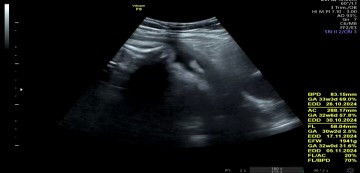

Sharing dong bund, ada nggak bunda² disini yang hasil FL (tulang paha janin) di usg.nya lebih pendek 2 minggu ? Harusnya 32w jadi 30w . Kemarin mau tanya ke dokter ga sempet ngelihat hasilnya. Sampe rumah baru dilihat kok kurang 2 minggu ya😩 #Sharing_dong_Bund #SeriusTanya #bantujawab #ingintahu